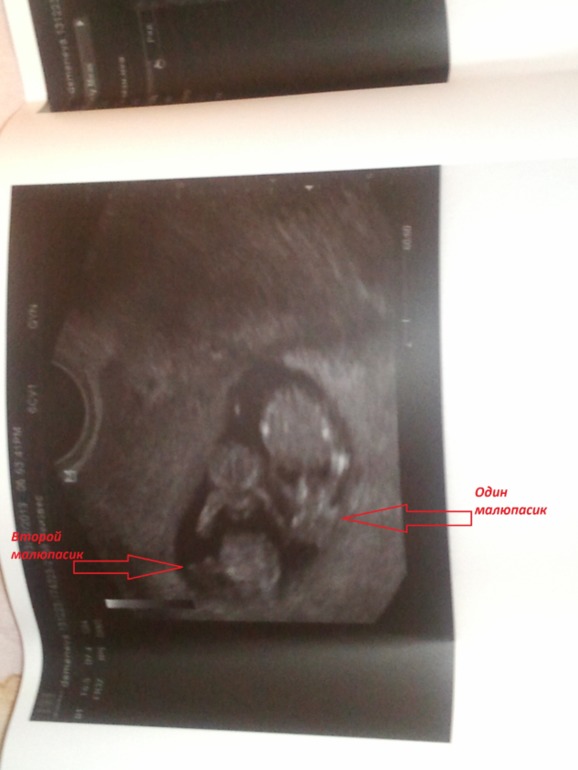

Я буду мамой двойняшек! Принимаем в наши рядыНу вот и я стала счастливой обладательницей двойного счастья. И так коротко о нас: нам 12 недель, по результатам узи подозрение на монохориальную биамниатическую двойню. Малышики практически одинаковые в развитие с разницей в 2-а дня. Ктр первого 47,8 (11 н 4 дня) второго 43,6 ( 11нед 2 дня). Узи делала 23.12.2013. Из минусов: детки прикрепились по задней стенке полностью перекрыв внутренний зев. Ну а в остальном все хорошо.

Ну а вот и мои пупсята.